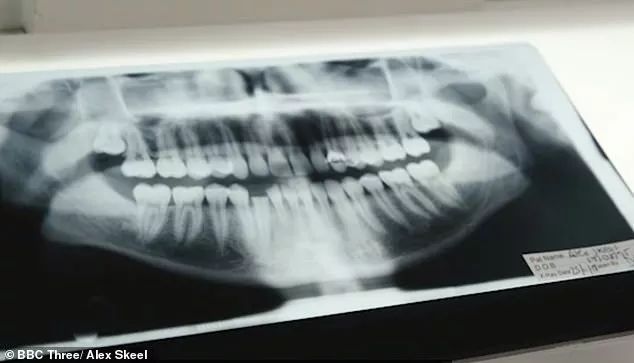

“有一次她打坏了我一颗牙齿,我兜里没有钱,也没法开车出去,只能自己硬生生地把牙齿掰断了。”